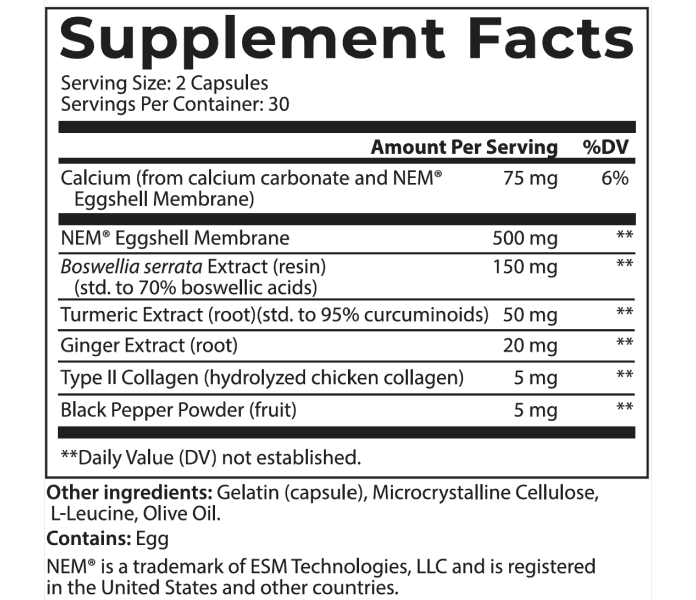

And to be 100% transparent, I’d like to show you the label that appears on every jar we ship.

Joint Support is an excellent addition to your daily routine…

And it’s so easy to use.

Simply take two capsules daily and that’s it.

In just a couple of seconds, you’ll take a huge step towards better joint health.

Personally, I recommend you take it first thing in the morning, like a daily multivitamin so you always remember to take it.